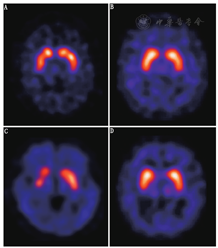

图2为继发性PS和ET代表性病例的DAT功能显像图。由于这部分患者的DAT结合力正常,其很容易与神经退行性PS患者(包括PD与aPS)相鉴别。然而,单凭基底节区123I-FP-CIT摄取正常或很轻微的减低并不能区分各类不同的继发性PS,亦不能鉴别继发性PS与ET。在这种情况下需结合临床,在某些情况下形态学影像亦有助于诊断(例如正常压力脑积水及血管性PS)。

1.震颤综合征。突触前DAT功能显像在震颤综合征和神经退行性PS的鉴别诊断方面有重要的临床应用价值。

(1) ET。ET是最常见的病理性震颤类型,其高峰发病年龄为青少年(20~30岁)和中老年(50~60岁)。超过一半的ET患者有家族史,呈常染色体显性遗传特征。ET的主要临床表现为对称性双侧肢体动作性震颤,亦可同时包含意向性震颤或静止性震颤(后者较少见)。患者通常首先由上肢开始,受累常为手臂,也可以累及头、颈、面部肌肉、发声系统和腿。从临床症状上ET和单一症状的神经退行性PS不易鉴别,DAT SPECT功能显像在这种情况下有其独特的临床应用价值。有时ET和PD可同时出现于一个患者,这种患者需要同时接受抗ET和抗PD治疗。10年前,欧洲多中心临床试验即针对ET和神经退行性PS鉴别诊断的难题展开研究,该试验结果推动了123I-FP-CIT在欧洲的批准使用[22]。该研究共纳入158例临床诊断为PS的患者,27例ET患者以及35名健康志愿者。结果显示,123I-FP-CIT SPECT显像可鉴别PS与ET,其灵敏度与特异性分别高达97%与100%。ET患者的DAT SPECT图像与健康志愿者相同,因而很容易与神经退行性PS患者相鉴别。相似的临床试验在后期被多次重复,证实了结论的可靠性。近期有类似研究对患者进行了更长时间的随访,最长的一项临床随访时间为3年[47]。这些研究的目的与之前相同,仅是研究方法有些差异,比如:有研究[35]在入组的震颤综合征患者中包括了SWEED和肌张力障碍性震颤患者,有研究[48]是通过DAT显像的半定量分析结果来鉴别ET和健康志愿者或偏侧症状的PS。